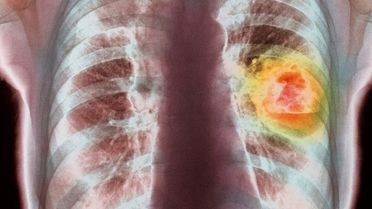

İskoçya'daki Edinburgh Üniversitesi'nde yapılan bir araştırma, altın zerreciklerinin, kanserle mücadelede kullanılan ilaçların etkisini artırabileceğini gösterdi.

İskoçya'da yapılan araştırmanın sonuçlarına göre zeytin yağındaki oleik asitin kanser hücrelerini engellediği ortaya çıktı.